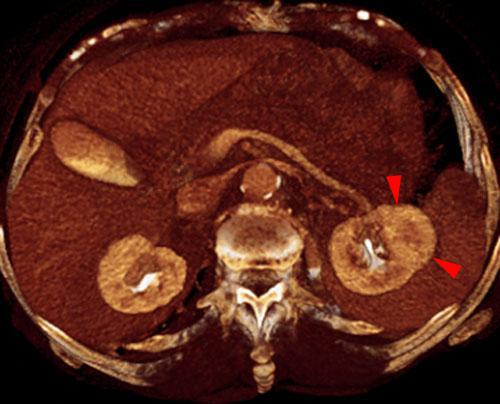

Quiste renal hemorrágico

VR seccional. Visión axial caudal. En esta serie contrastada se visualiza una lesión nodular (puntas de flecha) de aspecto heterogéneo con captación del contraste. El diagnóstico anatomopatológico fue quiste hemorrágico